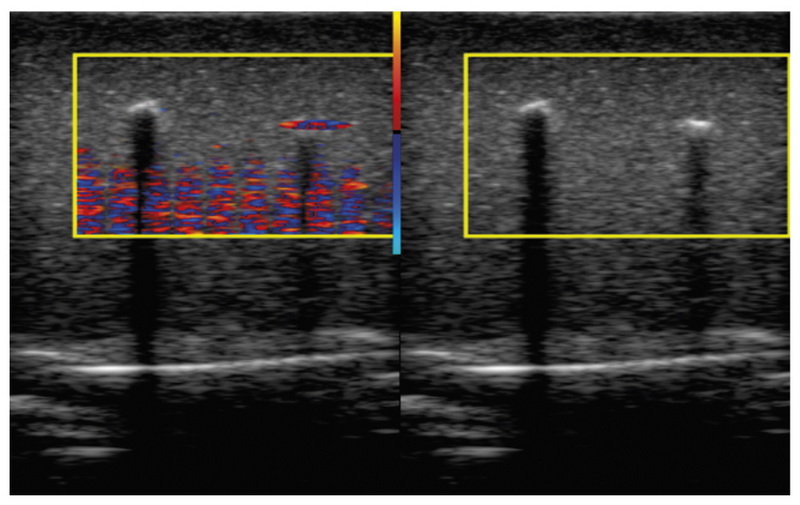

BACKGROUND: Doppler twinkling artifact is a rapid change of colors seen in CFI-mode in the presence of kidney stones and calculi. Therefore, numerous researchers use the twinkling artifact as a diagnostic sign. However, this phenomenon is under-researched, because most assumptions concerning its causes are made based on pure visual observations of the scanner’s screen leaving the important steps of signal transformation hidden behind the “black box” curtains of ultrasound machines.

MATERIALS AND METHODS: Raw radiofrequency ultrasound signals were recorded in the phantom studies. The recorded echoes were received from objects that create the Doppler twinkling artifact and artificial blood vessels and soft tissues imitators. The data were collected between June 2016 and March 2021. Sonomed-500 with the 7.5 L38 and 3.4 C60 probes served as the research machine for the signal capture.

Data records: We present the database containing raw radiofrequency ultrasound signals from the beam former output of the research ultrasound machine. The dataset consists of CFI and B-mode echoes recorded from twinkling objects. Therefore, this database can be useful for those who test, develop and study ultrasound signal processing algorithms. Furthermore, the database is freely available online. The 10.5 GB database consists of echoes received from five phantoms. Raw radiofrequency signals were stored in the binary files; scanning parameters were stored in text files. The database is available at: https://mosmed.ai/datasets/ultrasound_doppler_twinkling_artifact.